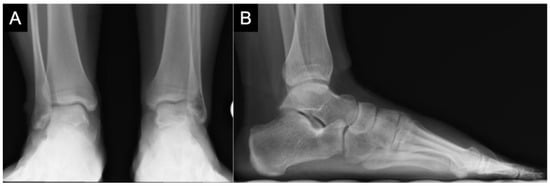

2. Etiology and Epidemiology

3. Diagnostics